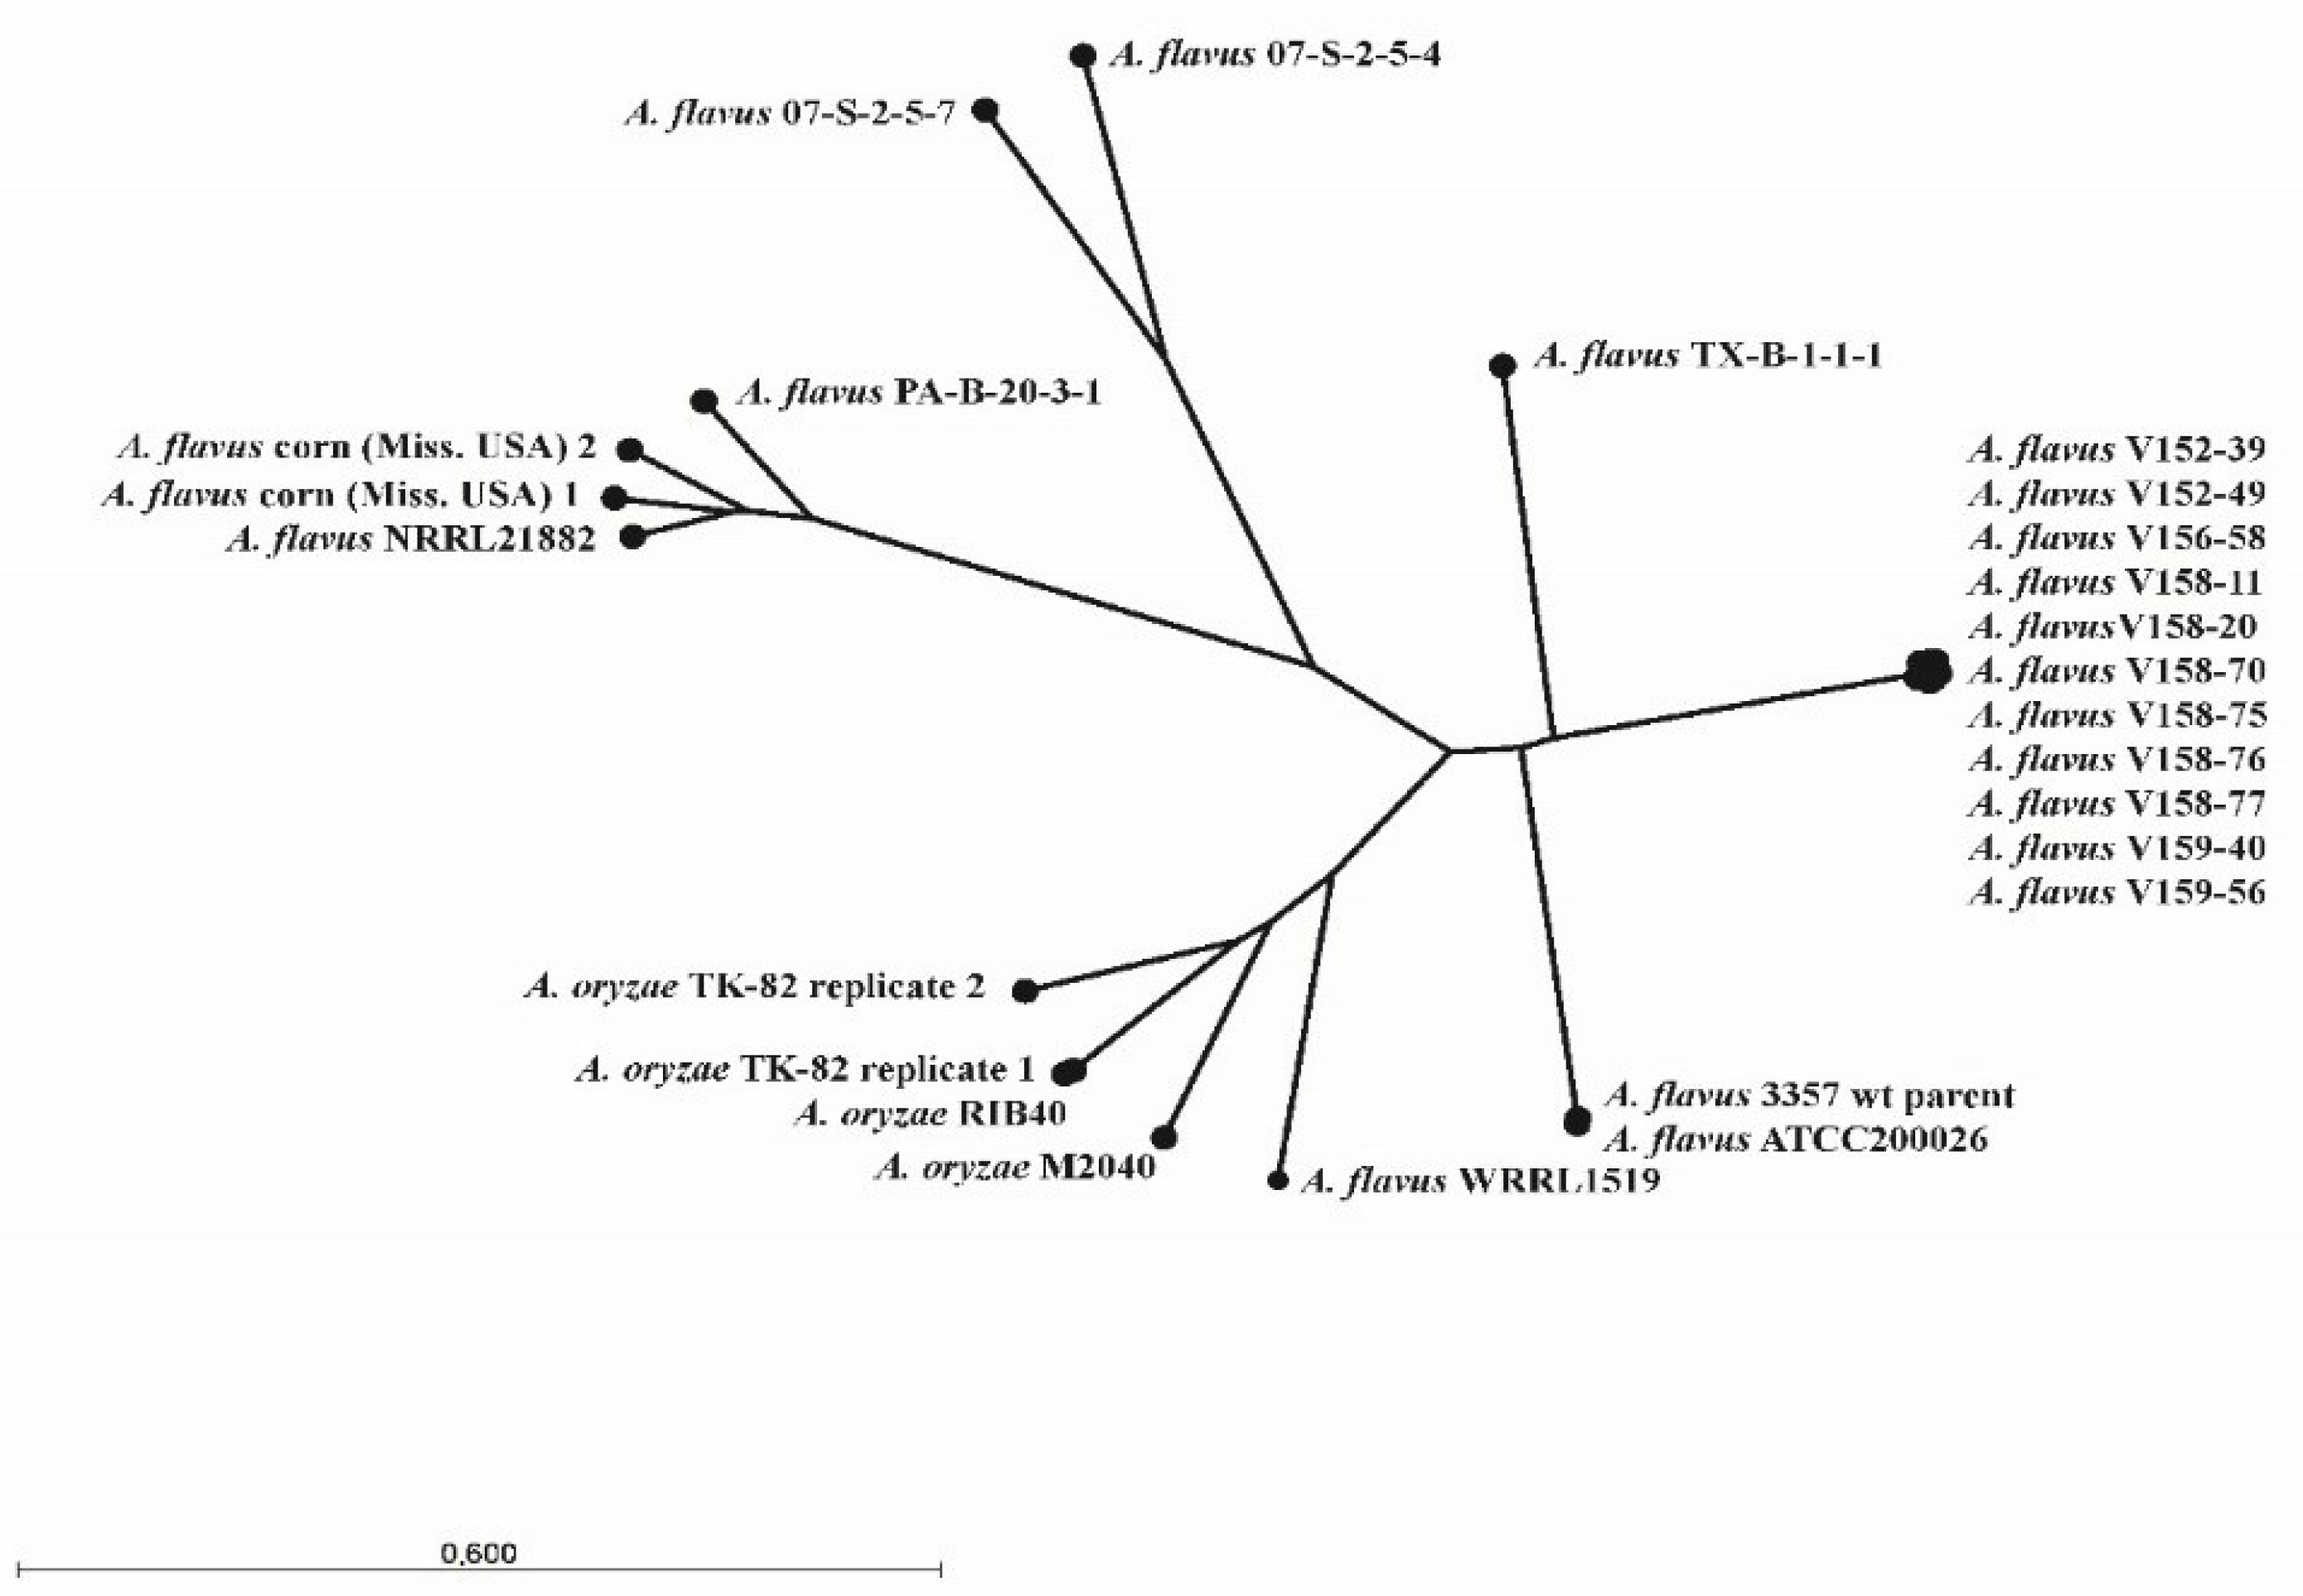

3.1. Strains, Phenotypical Analysis and Genotyping

3.2. Whole-Genome Sequence Analysis